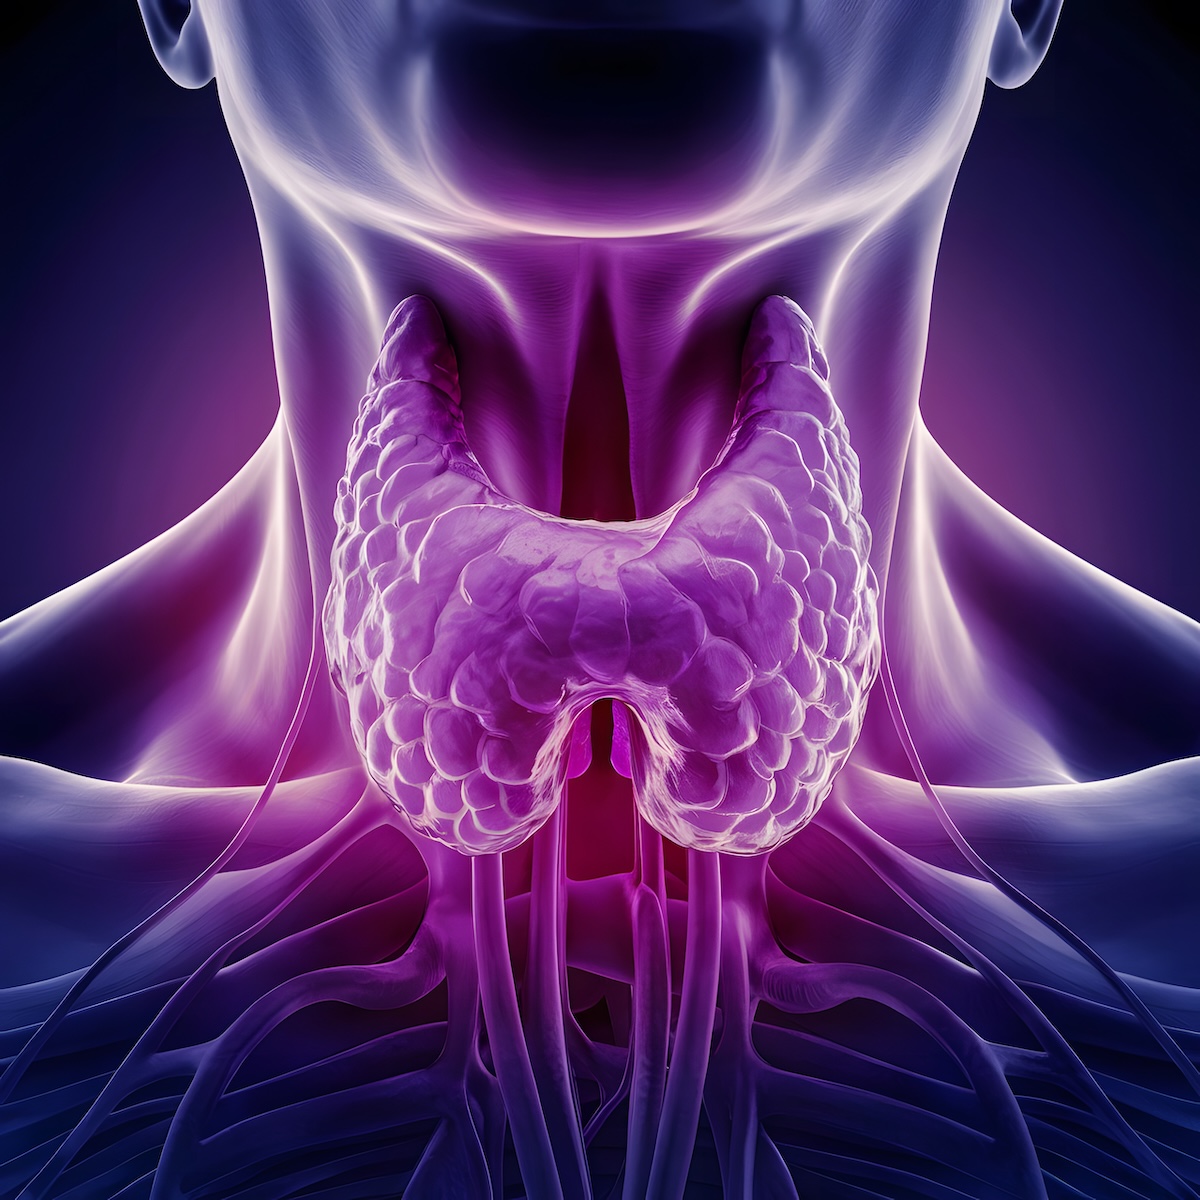

De schildklier zit aan de voorkant van je hals. Het is een kleine klier met een vorm die lijkt op een vlinder. Deze klier maakt belangrijke hormonen aan.

Het gaat om de hormonen T4 en T3. Deze stoffen regelen veel processen in je lichaam. Denk aan je hartslag, lichaamstemperatuur en energieverbruik.

Ook je spijsvertering en gewicht hangen samen met deze hormonen. Daarnaast hebben ze invloed op spieren en zenuwen. Zelfs je stemming en geheugen worden erdoor beïnvloed.